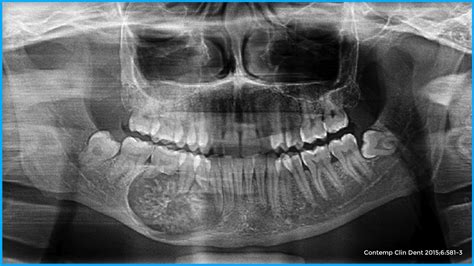

- Muelas del juicio: por último, otra de las causas más frecuentes de la aparición de fístulas orales es la erupción de las muelas del juicio o cordales. Si estos molares no erupcionan perfectamente la formación del bulto en la encía es una consecuencia.